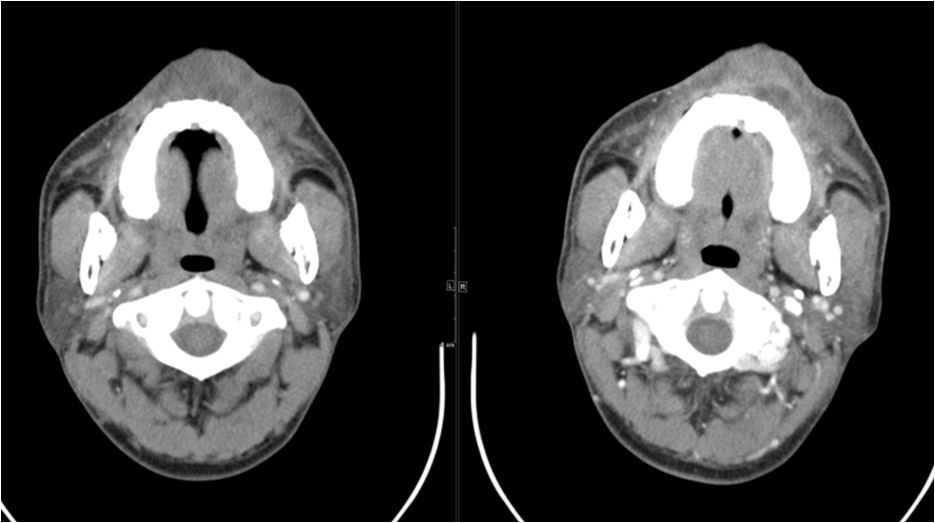

02 咀嚼肌间隙、翼下颌间隙、颊间隙

男,31岁,患者约3天前出现右侧面部口角区局限性肿胀,无明显触压痛,既往右侧下颌后牙区阵发性锐痛,曾自行口服消炎药处理,自诉牙痛症状无明显缓解,约3天前牙痛症状加重,伴夜间痛,后自觉右侧面部肿胀,约2天前开始发热,体温39.8℃。